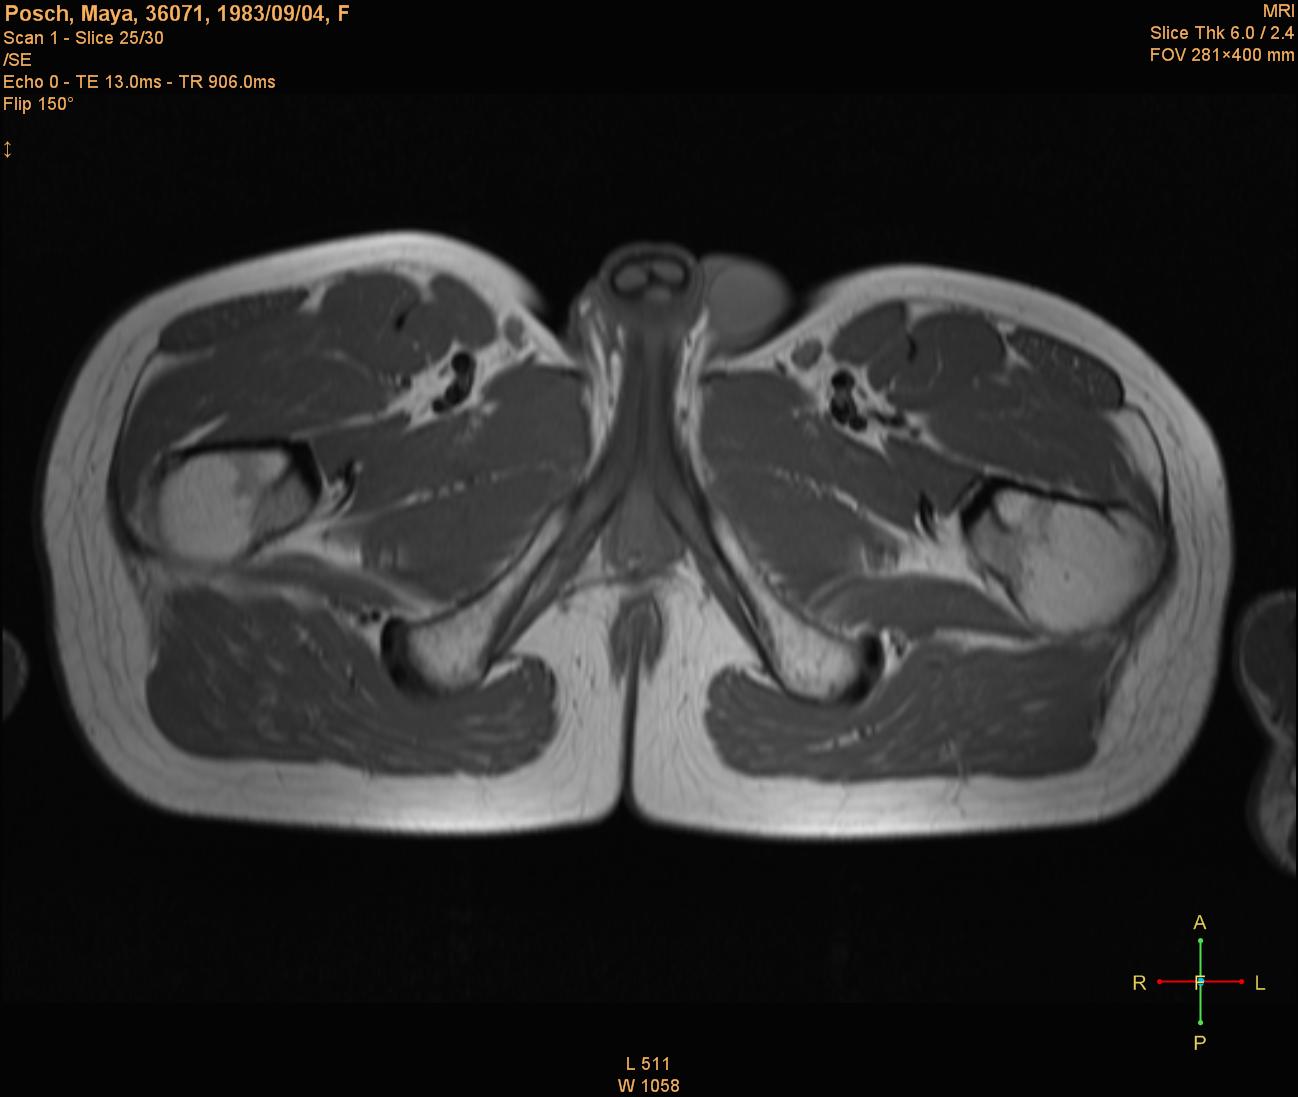

In the below MRI image it is clearly visible how one of both testicles (right side) appears to be missing.

Illustration

1: Missing testicle. Image from German MRI scan.